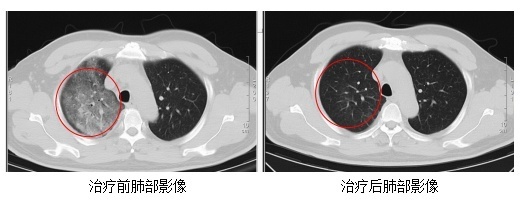

发烧门诊医师详确征询顾先生的既往病史,并为其进行缜密的体格查验。胸部CT后果骄慢,顾先生的双肺存在大面积的炎症病变。

在感染科医护团队的尽心诊疗与缜密防守下,顾先生的发烧、咳嗽、胸闷等症状逐渐缓解。复查的CT后果骄慢,肺部炎症情况赢得了澄莹的改善。现在,顾先生照旧顺利康复出院。